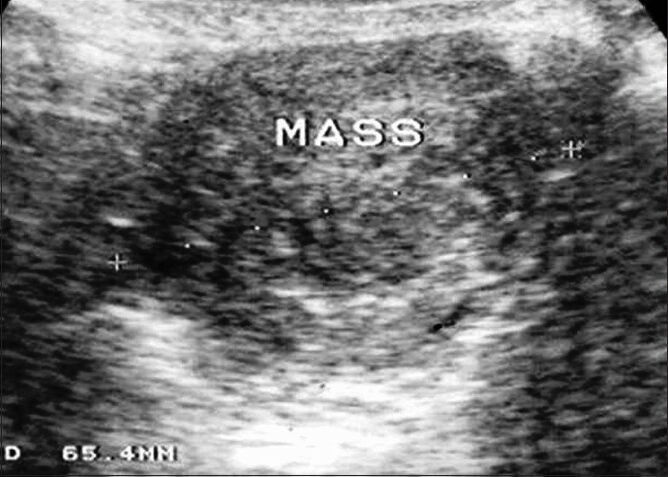

A non-communicating rudimentary horn is an uncommon site for ectopic pregnancy. Rudimentary horn pregnancy (RHP) is a rare entity but associated with grave clinical consequences. Majority of these cases if not detected timely end up in uterine rupture and present as an obstetrical emergency. We present this case of a 32-year-old, third gravida with a 12 weeks live gestation in the right rudimentary horn, which was successfully managed with laparoscopic resection. Early diagnosis is the key stone in the management of such cases. Laparoscopic resection is a safe and viable option in the surgical management of unruptured RHP.